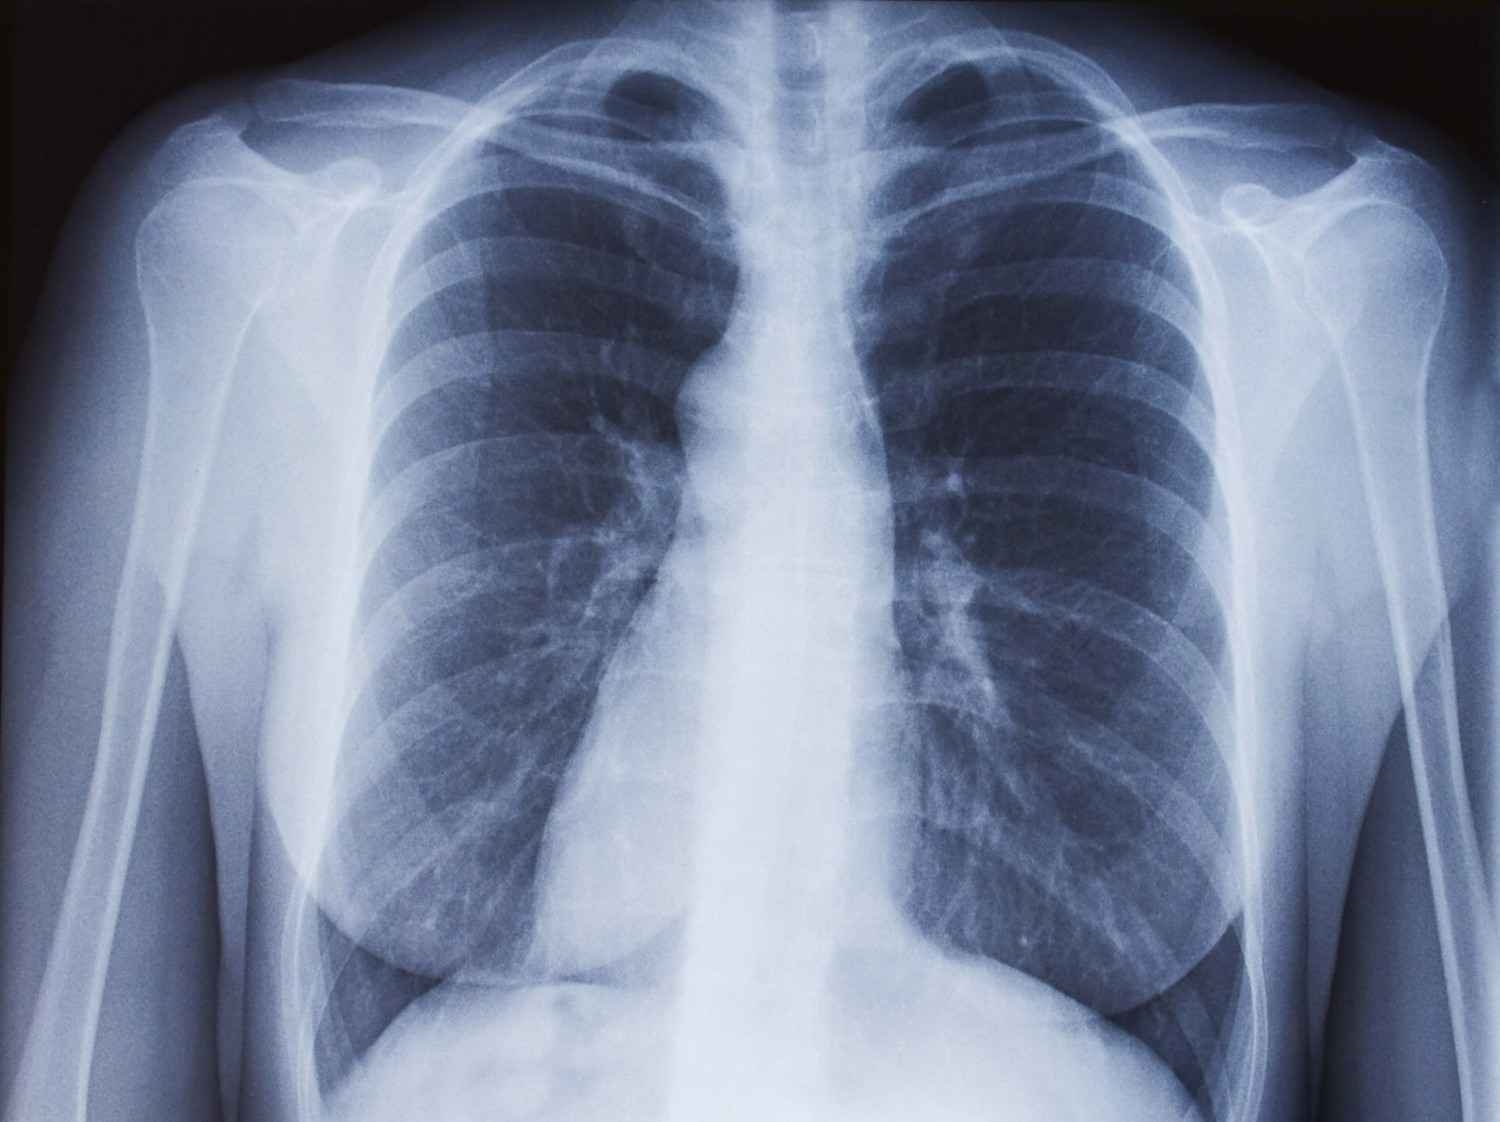

महराजगंज। ठंड बढ़ने के कारण जुकाम और बुखार के रोगियों की संख्या तेजी से बढ़ रही। युवाओं के साथ किशोरों के फेफड़ों में संक्रमण के मामले सामने आ रहे हैं। जिला अस्पताल की ओपीडी में शुक्रवार ऐसे 14 रोगी मिले। रिपोर्ट के आधार पर चिकित्सकों ने विशेष सावधानी बरतने की सलाह दी है।

शुक्रवार को जिला अस्पताल की ओपीडी में 778 मरीजों का उपचार हुआ। वायरल फीवर के रोगियों की अधिकता रही। युवाओं में ब्रोंकियोलाइटिस (फेफड़े की छोटी श्वास नली संक्रमण) के मामले भी 14 मिले। डाॅ. रंजन ने जांच रिपोर्ट के आधार पर संक्रमण की पुष्टि की। बताया कि ठंड में श्वसन संक्रमण बढ़ता है।

इसमें उपचार शीघ्र शुरू कराने की आवश्यकता होती है। इसे ब्रोंकियोलाइटिस रोग कहते हैं, इसमें लक्षण पहले सर्दी-जुकाम जैसे ही होते हैं लेकिन फिर स्थिति काफी खराब हो जाती है। बीमारी से पीड़ितों में खांसी और सांस छोड़ते समय गले से आवाज आती है और सांस छोड़ने में भी असुविधा होती है।

युवा व किशोर की इम्युनिटी वीक होती है और यह ठंड के प्रति बेपरवाह भी रहते हैं। इस वजह से वह फेफड़ों में संक्रमण की चपेट में आ रहे हैं। लेकिन घबराने की जरूरत नहीं हैं। त्वरित उपचार से यह एक सप्ताह में ठीक हो जाता है।